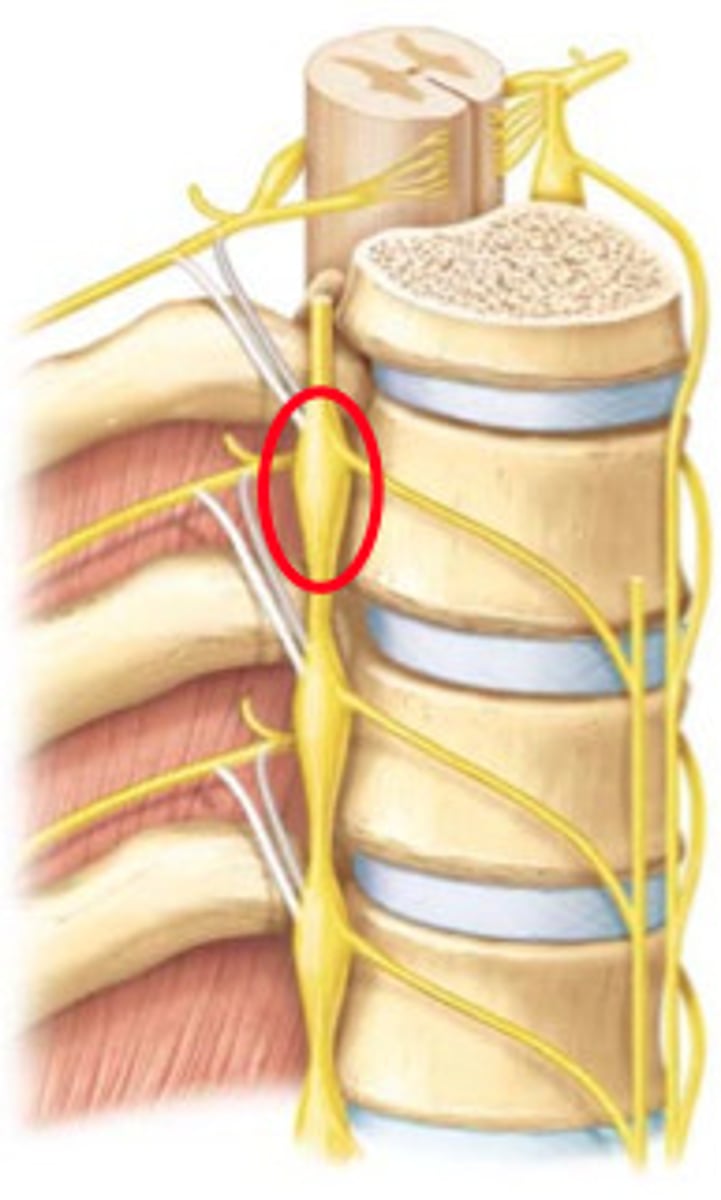

sympathetic trunk/chain ganglia

Runs along vertebrae, part of the sympathetic nervous system, keeps whole body in sync

White rami communicans

contain myelinated preganglionic fibers traveling to sympathetic trunk ganglia

gray rami communicans

contain unmyelinated postganglionic fibers traveling from ganglia to peripheral structures